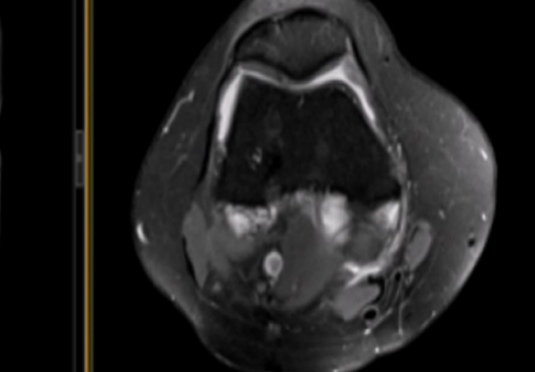

微創(chuàng)射頻消融術(shù)

適用于微創(chuàng)射頻熱消融術(shù)治療患者,引進(jìn)權(quán)威醫(yī)療團(tuán)體輔助引流。